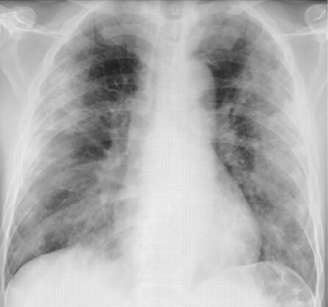

正常な肺

間質性肺炎

両側に肺が白く(スリガラス様)になる